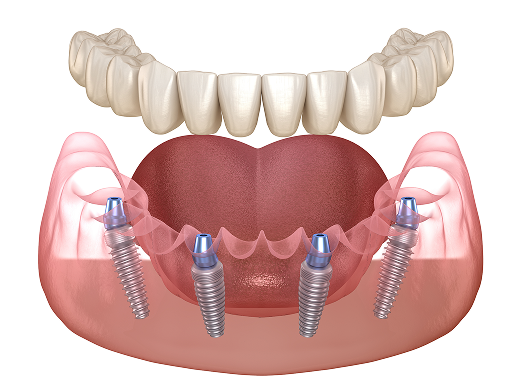

All-on-4(All-on-6)とは

All-on-4(オールオンフォー)は、4本のインプラントで、12本の歯を支える治療法です。従来の治療ではインプラントが8~10本必要だった部位を、 半分以下の4本で完了する画期的な技術です。

※ All-on-6(オールオンシックス)は6本のインプラントで支える治療法です。

最少本数での治療

4本のインプラントで全体を支えるため、治療期間の大幅短縮につながり身体や費用の負担を少なくすることが可能です。 骨移植が不要なケースも多く幅広い方に適応できる治療法です。